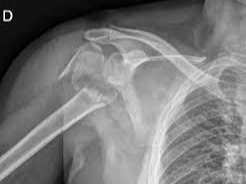

상완골 골절이란 무엇인가

상완골은 어깨부터 팔꿈치까지 이어지는 긴 뼈로, 어깨관절과 팔꿈치관절을 연결하는 핵심 구조입니다. 이 부위가 골절되면 단순한 통증을 넘어서 팔의 움직임 자체가 제한되며 일상생활에 큰 불편을 초래합니다.

- 근위부 골절: 어깨 관절 근처 골절